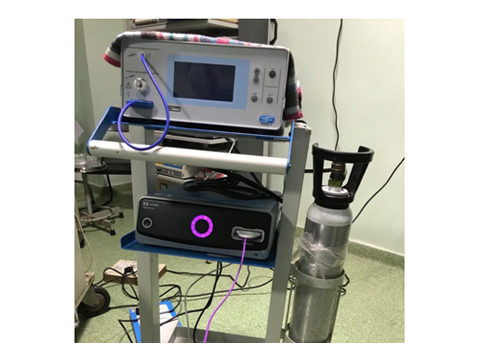

We have state of the art operating theatre with advanced surgical equipments. We have a Karl Storz Spies advanced HD laparoscopy operating system in addition to a 3 chip laparoscopy. We have installed advanced vessel sealing devices like Gen 11 harmonic scalpel, Ligasure from Valley Lab & Argon plasma coagulator. There is a recent addition of Cavitron Ultrasonic Aspirator (CUSA) system into our surgical armamentarium. We have the most recent powered Echelon endo-stapling devices. In addition to all these we have a constant supply of various types of advanced stapling devices for GI surgeries. Our endoscopy machines are having high definition with FICE Technology. Last but not the least we have semi flexible Ureteroscopy for managing common bile duct stones.

ARGON PLASMA COAGULATOR